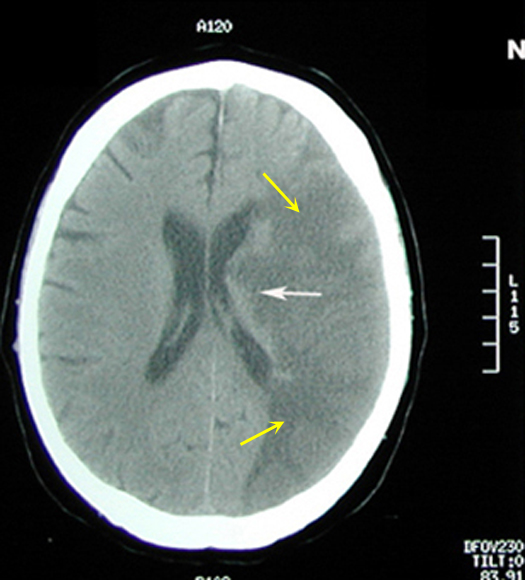

Figure 1: Non-contrast axial CT brain

Acute to Subacute Infarct

Case 1:

Imaging findings: Figure 1

- Large area of low CT attenuation (hypodense) is seen involving the left middle cerebral artery distribution (yellow arrows), with involvement of both gray and white matter.

- White arrows points to involvement of basal ganglia region with infarction also.

- Gyri and sulci are effaced on the left side (compare to normal right side).